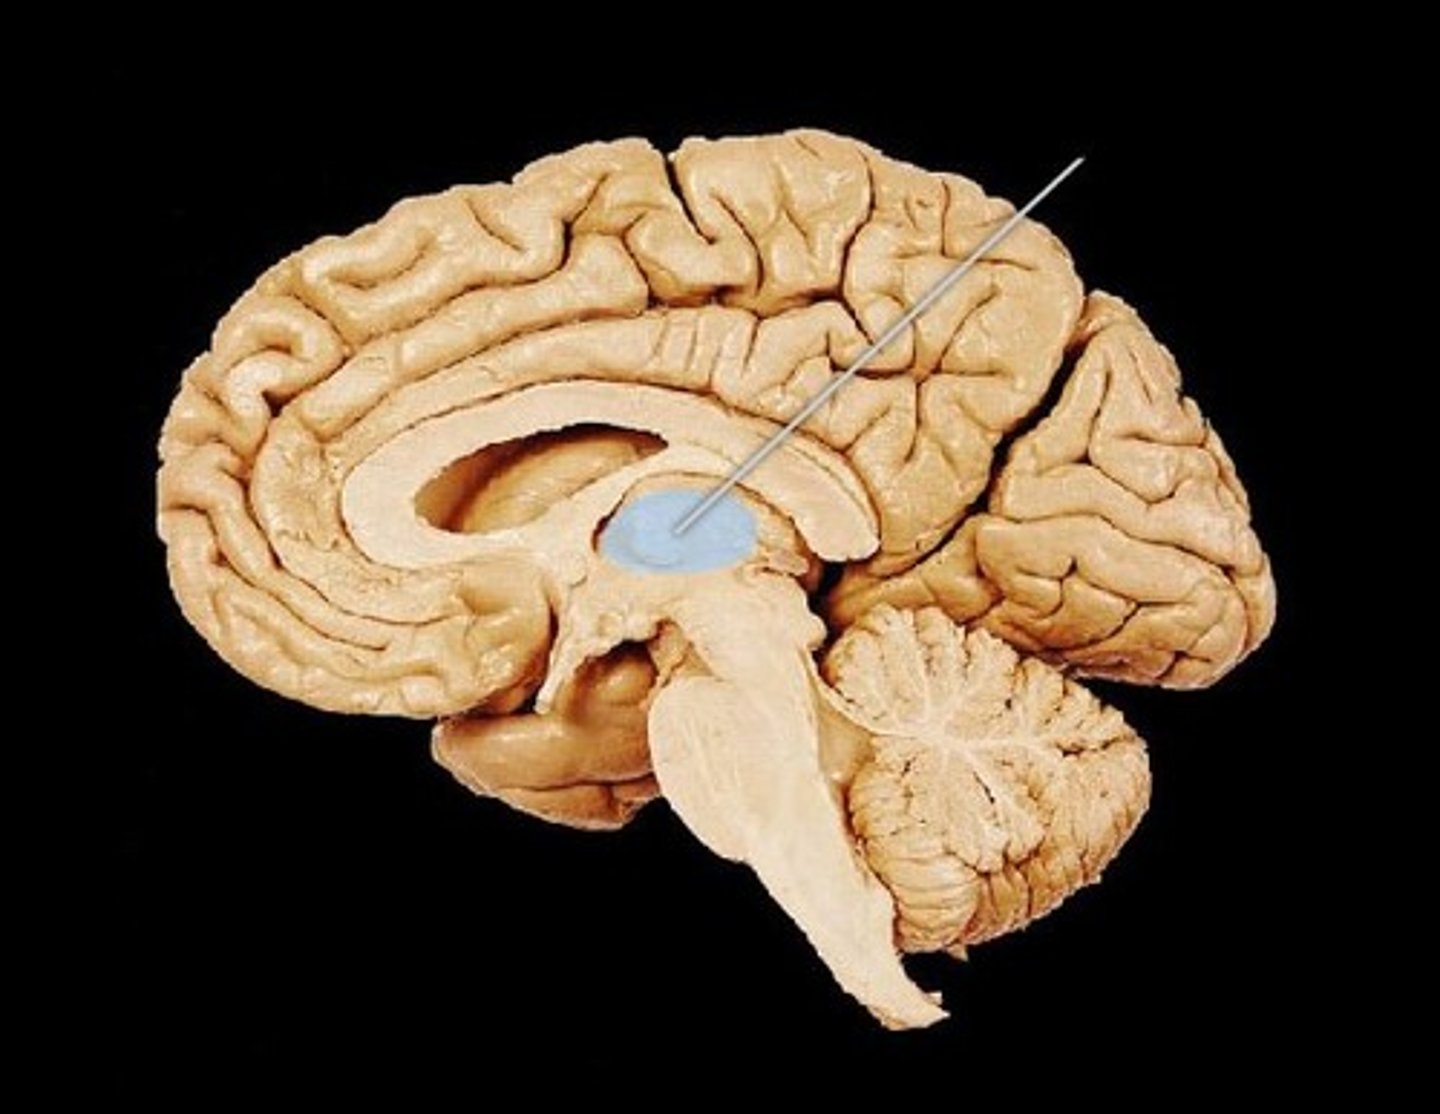

Parts of the brain

- cerebrum

- brain stem

- cerebellum

Parts of the brain: cerebrum

- the bulk of the brain

- made up of the telencephalon and the diencephalon

Diencephalon

- 2nd layer of the cerebrum (deep to the telencephalon)

- the core of the cerebrum, surrounded the bat cerebral hemispheres

- responsible for sensory and motor relay into and out of the brain, as well as control over the autonomic nervous system

parts of diencephalon

thalamus and hypothalamus

- encloses the 3rd ventricle

diencephalon: thalamus

- 2 bodies, 1 per hemisphere

- this part of the brain is responsible for relaying sensory information (except sense of smell) to other areas of the brain

Diencephalon: Hypothalamus

- small structure below the thalamus that is commented to the pituitary gland

- controls the release of hormones through the pituitary gland

Support and Protection of the Brain: Ventricles

- also provides support and protection to the Brain

- made up of 4 hollow spaces that are continuous with each other and the spinal cord

- these spaces contain cerebral spinal fluid

lateral ventricles (2)

third ventricle

fourth ventricle

Ventricles: Lateral Ventricles

- paired "C" shapes spaces deep within the cerebral hemispheres

- a portion of the lateral ventricles can be found in each lobe

Ventricles: Third Ventricle

- 1

- located in the middle of the diencephalon between the 2 halves of the thalamus

- connected to the lateral ventricles by the

interventricular foramina